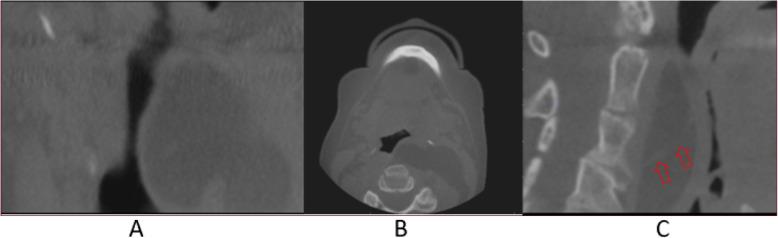

A 66-year-old female presented for a pre-implant CBCT with no history of other complaints or signs/symptoms. CBCT imaging depicts a large, well-defined, low-attenuation/soft tissue density lesion with an undulating appearance extending from the posterior left pharyngeal wall and occluding two-thirds of the airway from C2 to C4. The lesion extends laterally into the left parapharyngeal space and inferiorly beyond the field of view of the study. Evidence of faint internal septations was noted. The patient was immediately referred for an ENT consult. Laryngoscopy, MRI, and contrast-enhanced MDCT imaging were conducted to determine the full extent and nature of the lesion, as well as to potentially plan for biopsy and/or surgical resection. Removal of the lesion was successful, and histopathologic evaluation confirmed lipoma. Periodic follow-up was recommended to monitor for possible recurrence.

一名66岁女性因种植前CBCT检查前来就诊,无其他既往病史或体征/症状。CBCT成像显示一个大的、边界清晰的、低衰减/软组织密度病变,呈波浪状外观,从左咽后壁延伸,阻塞了从C2到C4三分之二的气道。病变向外侧延伸至左咽旁间隙,向下超出研究视野范围。可见微弱的内部间隔迹象。患者立即被转诊至耳鼻喉科会诊。进行了喉镜检查、MRI和增强MDCT成像,以确定病变的全貌和性质,并可能为活检和/或手术切除制定计划。病变切除成功,组织病理学评估证实为脂肪瘤。建议定期随访以监测可能的复发情况。